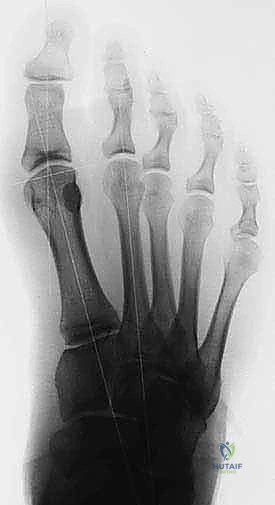

Isolated complete sesamoidectomies are thought to alter the mechanical balance of the hallux MTP joint. Clinical studies have described stiffness, functional loss, cock-up deformity, claw toe deformity, and the development of a hallux valgus deformity after isolated tibial sesamoidectomies. 8,9,11,12

As noted earlier, identifying and addressing any significant malalignment of the hallux MTP can decrease the rate of future deformities.

FIG 10 • Preoperative ( A ) and postoperative ( B ) standing radiographs of the foot showing no change in the clinical alignment of the metatarsophalangeal joint after tibial sesamoidectomy. (From Lee S. Technique of isolated tibial sesamoidectomy. Techn Foot Ankle Surg 2004;3:85–90, with permission.)